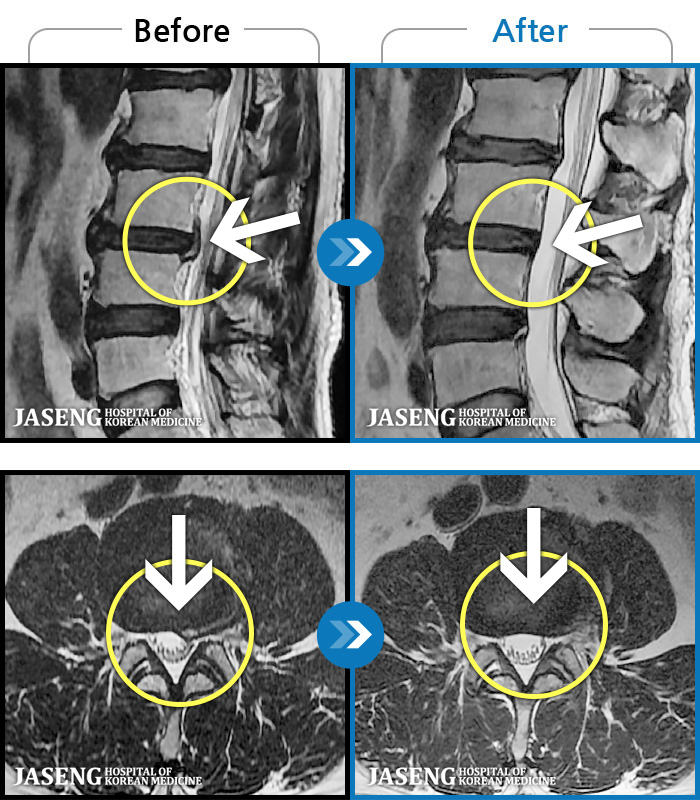

허리디스크

도움받은 사례

해운대 · 김상돈 원장

하지 저림과 통증이 개선되어서 일상생활이 너무 즐겁습니다.

촬영시기

2023.09.18 ~ 2025.01.27

2025.02.05

조회수 16,646